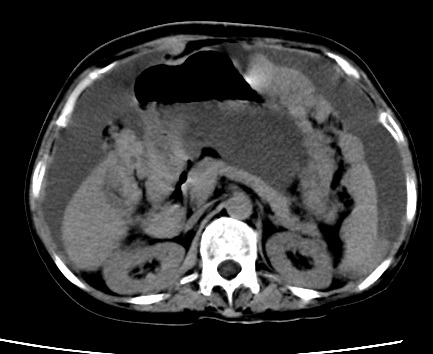

标题: CT23975:女61岁,腹部不适,明显消瘦 [打印本页]

标题: CT23975:女61岁,腹部不适,明显消瘦

既往5年前卵巢癌行子宫及附件切除,右乳癌术后一年,考虑腹膜转移?

支持楼主!(腹膜 网膜均有转移)

1)结合病史,考虑腹膜及网膜转移瘤。2)肝脏多发性低密度灶,不排除转移瘤。3)大量腹水。

腹膜 网膜均有转移

考虑卵巢癌行子宫术后复发,并肝、腹腔 、大网膜转移可能性大。

大量腹水。